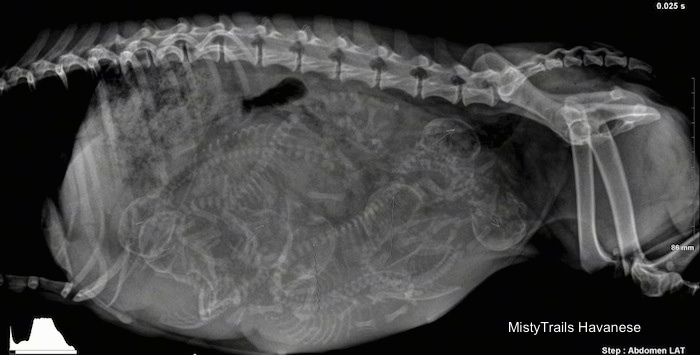

Для того, чтобы сделать рентгеновский снимок с целью диагностики беременности, необходимо положить животное на бок и/или на спину. Эти позиции позволяют провести подсчёт количества плодов. Обычно считают количество скелетов (позвоночников или черепов). Наиболее точное определение возможно на более поздних сроках, начиная с восьмой недели беременности.

Чаще всего до родов рентгенографию используют для определения размера помета, а после родов — для гарантии, что родились все щенки. На рентгенограммах небеременных сук редко можно обнаружить матку.

У беременных сук увеличение матки можно зафиксировать только на 21-й день беременности. С 21-го но 42-й день беременности можно видеть увеличенные, наполненные жидкостью рога матки. Скелеты плодов становятся рентгенонепрозрачными на 44-47-й день беременности или на 35 40-й день диэструса, а череп и позвоночник становятся видны раньше длинных костей и костей пальцев. Для постановки точного диагноза беременности нужно 2 дня (Сопсаппоп andRendano, 1983). Зубы плодов различают на 58 63-й день. Если основываться на дате первой вязки, то минерализацию скелета можно идентифицировать уже на 42-52-й день после вязки После 47-го дня беременности, когда скелеты плодов будут минерализованы настолько, чтобы стать рентгенонепрозрачными, но рентгеновским снимкам можно определить размер помета. Он зависит от многих факторов, но чаще всего у мелких пород в — будет 2- 4 щенка, у средних пород — 4 7, а у крупных собак от 6 до 10 щенков. Рентгенография позволяет точно подсчитать численность малого помета, но даже несмотря на се более высокую точность но сравнению с ультрасонографией, на рентгеновских снимках нс всегда возможно подсчитать количество щенков в больших пометах. Самый легкий путь определения размера помета — подсчет количества черепов и позвоночников на рентгеновских снимках (рис. 8 и 9).

С помощью рентгенографии можно подтвердить жизнеспособность плодов по отсутствию внутриматочных плодных MCuiKOB, наполненных газом, или деформации и изгиба частей скелета, что происходит после гибели плодов (рис 10).

Также по рентгеновским снимкам можно определить размер черепа для сравнения его с тазовой полостью суки. Сильно беспокоящиеся владельцы могут потребовать рентгенографию брюшной полости, чтобы предсказать предстоящие роды. Однако если нет слишком больших плодов (1-2 в помете), то измерение скелетных элементов плодов малоинформативно в предсказании трудности предстоящих родов. Рентгенографию также используют для проверки, нс остались ли нерожденные щенки после явного окончания родов

Щенки щенков

Ниже приведены различные рентгенограммы беременных дам, которые вот-вот родятся. Некоторые из них обозначены позициями щенков, чтобы помочь вам лучше понять, как определять щенков.

Целесообразно сделать рентген плотины за день или два до родов. Это отличный инструмент не только, чтобы показать вам, сколько, но и размеры и позиции щенков.Этот рентген был сделан за три дня до рождения щенков.

Этот рентген был сделан за день до рождения щенков. Вы можете видеть одного щенка, участвующего в родовом канале. Она в течение 24 часов с момента доставки.

Рентгенс изображением трех щенков.

Рентген с изображением четырех щенков.

Если вы сделаете рентген в дни 55/56/57, то сможете увидеть головы, позвоночники, ребра и ноги.Сначала посчитайте головы, а затем найдите позвоночник, который будет идти с каждой головой. На этом рентгеновском снимке точно показаны шесть щенков одинакового размера, и ничего страшного. Там может быть семь щенков, с возможностью восьми. Смотрите рисунок ниже, чтобы помочь найти щенков

На этой картинке изображены щенки, которых можно увидеть наверняка.